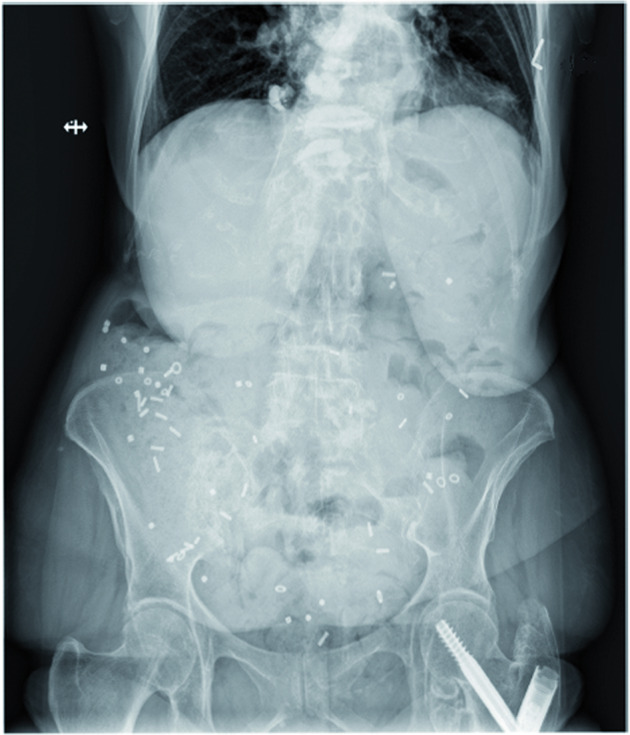

Revisamos el conocimiento actual sobre la fisiopatología, la fisiopatología, el diagnóstico y el tratamiento del tracto gastrointestinal en la enfermedad de Parkinson  y brindamos recomendaciones para el manejo en la práctica diaria. npj Parkinson's Disease, 22 de marzo de 2022